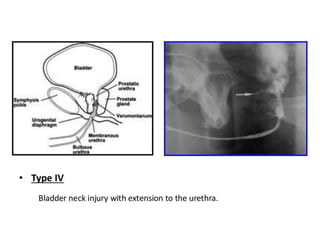

This document discusses the considerations and precautions for retrograde urethrography (RGU), noting that local anesthetic may cause issues such as mucosal edema. It highlights the need for antibiotic coverage due to potential complications like extravasation during contrast injection, and touches upon the role of cystography in pelvic fractures, indicating it can often be safely omitted. Additionally, it reports on complications related to urinary tract infections and reactions to contrast media, offering recommendations for patient management.